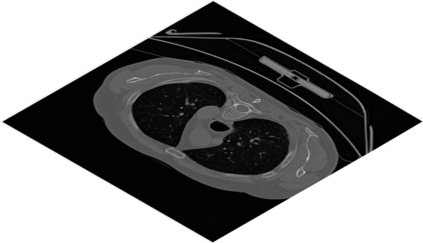

Deep Convolutional Neural Networks (DCNNs) are used extensively in biomedical image segmentation. However, current DCNNs usually use down sampling layers for increasing the receptive field and gaining abstract semantic information. These down sampling layers decrease the spatial dimension of feature maps, which can be detrimental to semantic image segmentation. Atrous convolution is an alternative for the down sampling layer. It increases the receptive field whilst maintains the spatial dimension of feature maps. In this paper, a method for effective atrous rate setting is proposed to achieve the largest and fully-covered receptive field with a minimum number of atrous convolutional layers. Furthermore, different atrous blocks, shortcut connections and normalization methods are explored to select the optimal network structure setting. These lead to a new and full-scale DCNN - Atrous Convolutional Neural Network (ACNN), which incorporates cascaded atrous II-blocks, residual learning and Fine Group Normalization (FGN). Application results of the proposed ACNN to Magnetic Resonance Imaging (MRI) and Computed Tomography (CT) image segmentation demonstrate that the proposed ACNN can achieve comparable segmentation Dice Similarity Coefficients (DSCs) to U-Net, optimized U-Net and hybrid network, but with significantly reduced trainable parameters due to the use of full-scale feature maps and therefore computationally is much more efficient for both the training and inference.